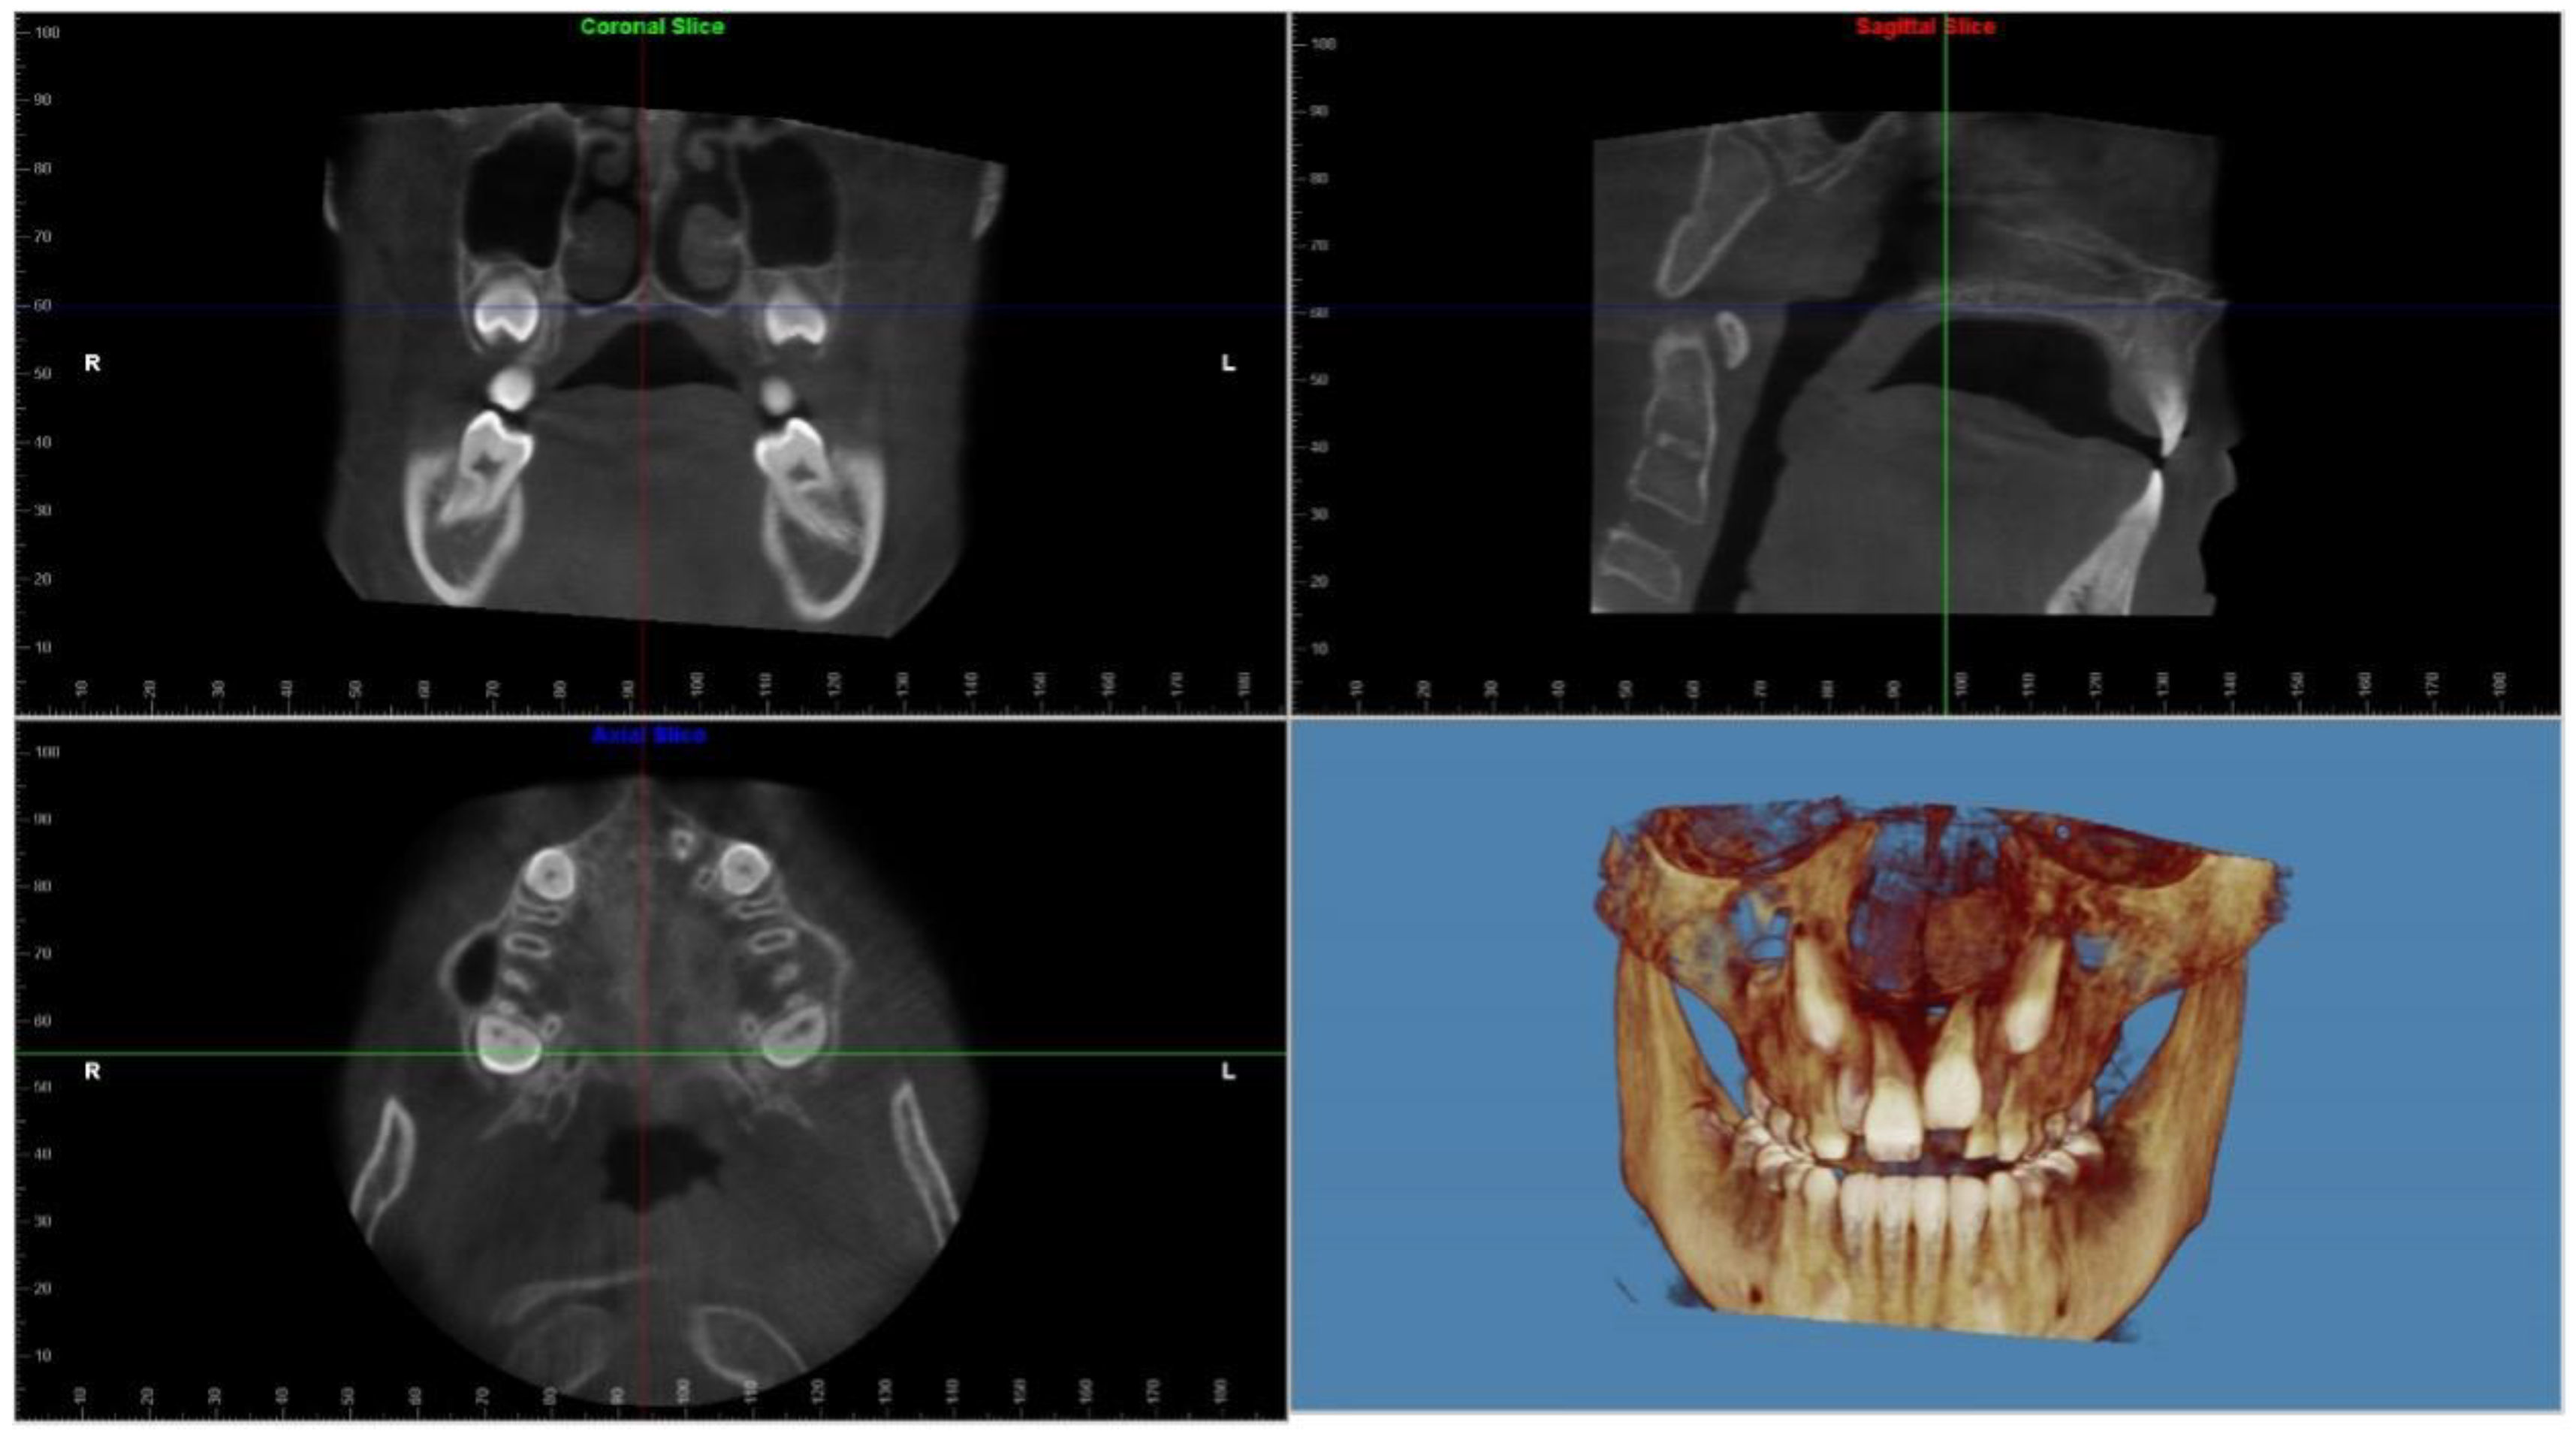

- El, H.; Palomo, J.M. Measuring the airway in 3 dimensions: A reliability and accuracy study. Am. J. Orthod. Dentofac. Orthop. 2010, 137 (Suppl. S4), S50.e51–S50.e59. [Google Scholar] [CrossRef]

- El, H.; Palomo, J.M. Three-dimensional evaluation of upper airway following rapid maxillary expansion: A CBCT study. Angle Orthod. 2014, 84, 265–273. [Google Scholar] [CrossRef]